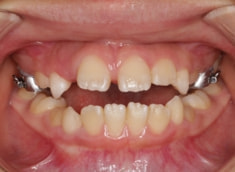

治療前